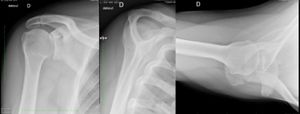

Plain Radiographs

The views that should be included in the workup are a true anteroposterior view (grashey view), internal and external rotation view, a scapular Y view, and a Bernageau view. Posterior dislocation is missed initially on posteroanterior radiographs in 50% of cases, as the humeral head appears to be almost normally aligned with the glenoid.

Anteroposterior view

Acute

On anteroposterior view, an overlap of the head in relationship to the glenoid can be observed (trough line sign, loss of the normal half-moon overlap sign, Figure 15). Moreover, an internally rotated humeral head gives a rounded appearance, which is called the lightbulb sign. Furthermore, the rim sign is defined as the space between the anterior glenoid rim and the humeral head being > 6 mm indicating a widened glenohumeral space (Figure 16).[18]

Scapular Y View (Neer)

The scapular Y view can demonstrate a posterior translation of the humeral head (Figure 18).

Axillary view

As a Bernageau view is difficult to obtain in acute cases because of severe pain, Velpeau axillary views is an alternative (Figure 19).[19]